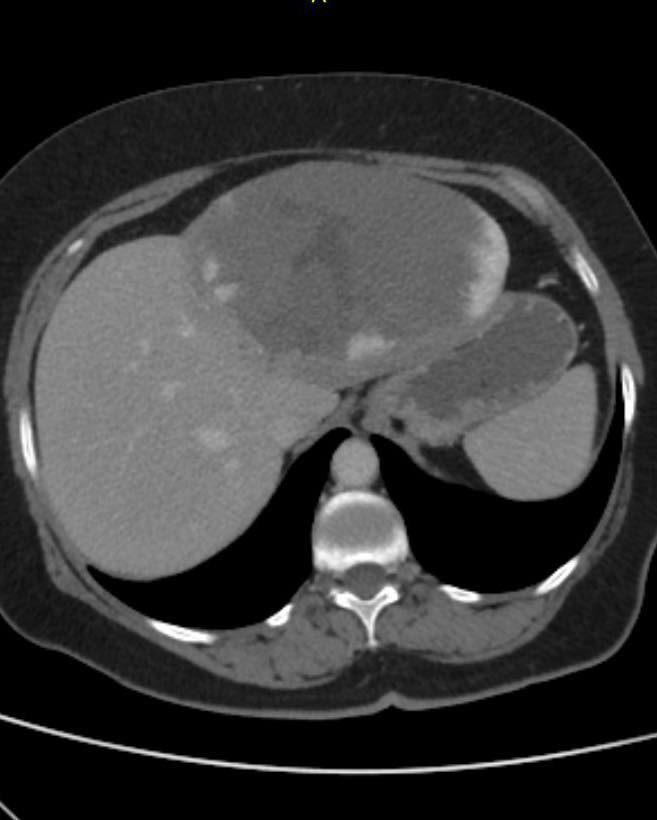

Рівненські онкохірурги успішно прооперували 15-сантиметрову пухлину печінки

Гемангіома печінки - найпоширеніша доброякісна пухлина цього органу. Вона трапляється у 2–20% населення і в більшості випадків не викликає симптомів та не потребує лікування.

У нашому центрі ми отримали рідкісний випадок - пацієнтка, 64 роки, раніше проходила лікування в Рівненському обласному протипухлинному центрі та щороку перебувала під КТ-контролем у межах follow-up.

За рік гемангіома печінки збільшилась з 4 см до 15 см, що стало прямим показом до оперативного лікування.